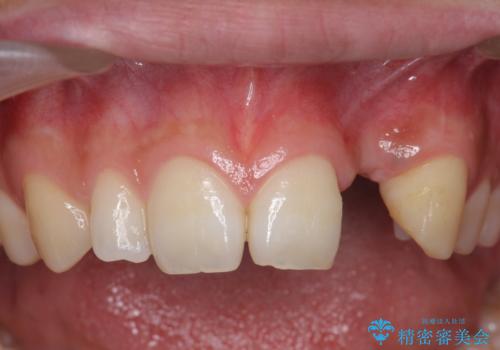

- 前歯の永久歯が元々なく、乳歯を失ったタイミングで前歯の審美性の回復を求めて来院されました。

機能・審美性の回復手段として、インプラント治療・ブリッジ・部分床義歯が考えられます。

それぞれの治療に特徴がありますが、取り外しの必要がなく隣の歯を削る必要も必要ないインプラント治療を選択されました。

前歯部にインプラントを埋入し、きれいに仕上げるためには骨の造成技術や歯肉の厚みを増すような処置を行い、インプラント周囲の環境を整備することが肝要です。